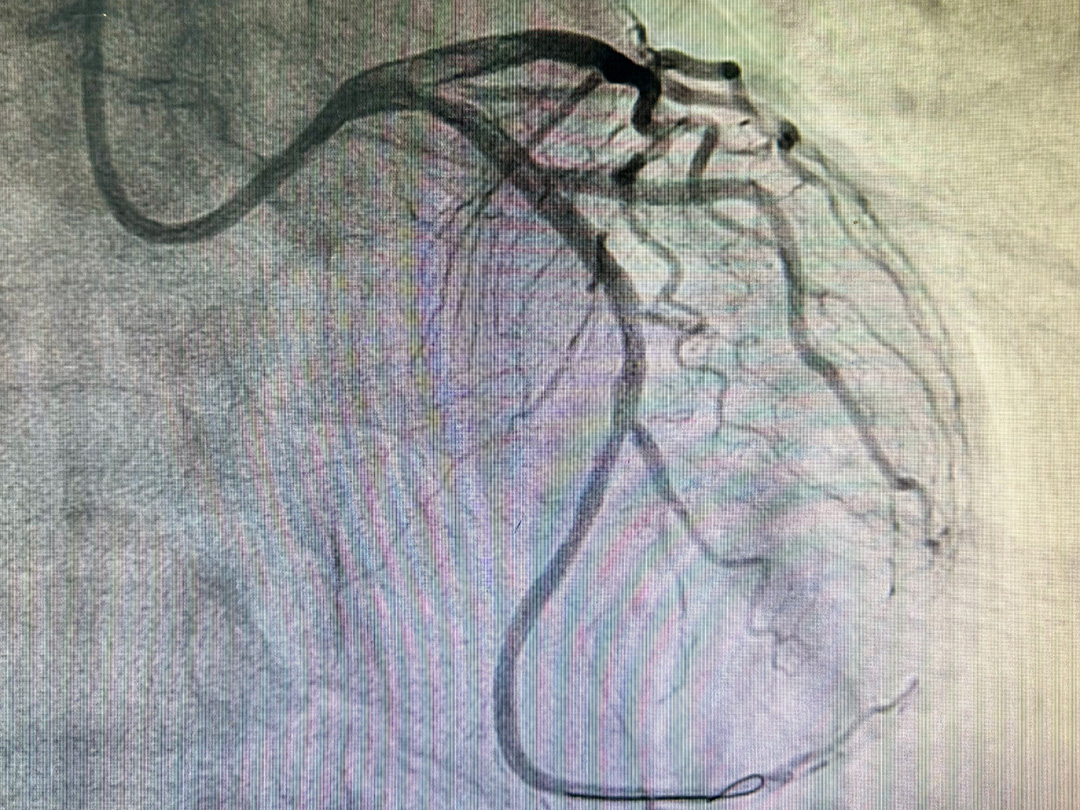

快速开通闭塞血管并实施药物球囊扩张成形术

术前

术后

明确诊断后,我院导管室团队为患者实施药物球囊扩张术,撑开血管并释放药物后,球囊完整撤出,体内不遗留任何异物,患者胸痛症状即刻消失。